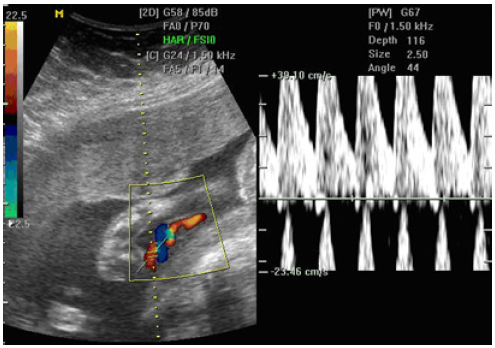

O fenômeno abaixo está relacionado a:

Artefato Twinkling

Aliasing